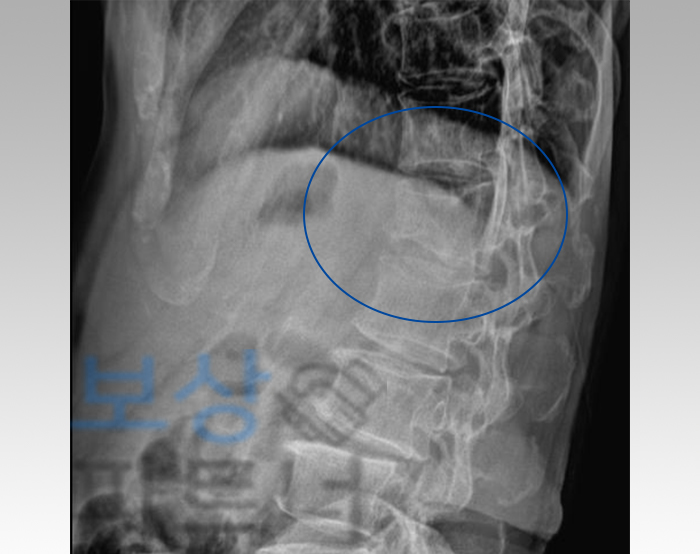

진단 결과는 L1 부위의 골절, 즉 요추 1번 압박골절이었습니다. 허리 부위의 척추체가 찌그러지듯이 골절되신 것이죠. 이런 경우 부상도 문제이지만, 이후의 사건 처리가 정말 복잡하다고 할 수 있습니다. 하지만 K 님께서는 일반인과 마찬가지로 보상에 대한 전문 지식이 없으셨기 때문에, 상대방 포크레인 기사의 자동차보험에서만 일단 배상을 받으려고 하셨습니다.